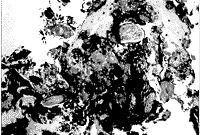

病理组织学检查所见证实囊壁为非角化复层鳞状上皮含有杯状细胞(图4)。在上皮表面发现了表示变性的脱落上皮细胞的蛋白质性质物质。囊壁含有毛干、皮脂腺和炎性细胞(图5)。所有的切片均与起源于结膜的皮样囊肿诊断相符。

图4 囊肿由非角化鳞状上皮作衬里。过碘酸席夫阳性的基底膜异常增厚